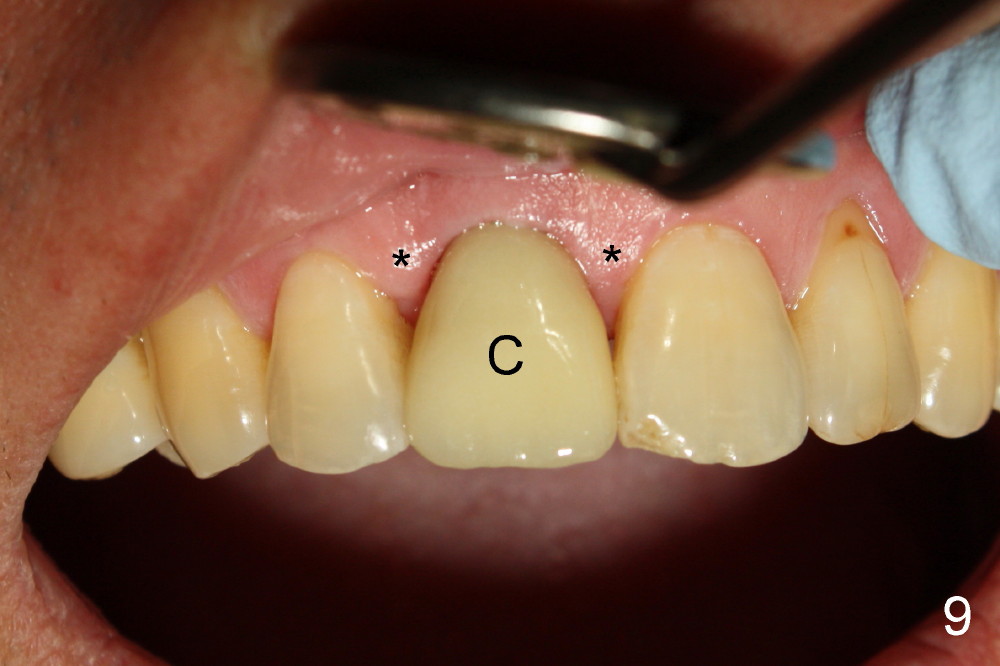

The provisional is dislodged 3.5 months postop; there is no labial atrophy (Fig.8 black arrowhead). The permanent crown (Fig.9 C) is harmonious with the papillae (*). When the try in crown is removed, the gingival tissue looks healthy (Fig.10 *).

Fig.11,12 are taken 6,18 months post cementation, respectively.